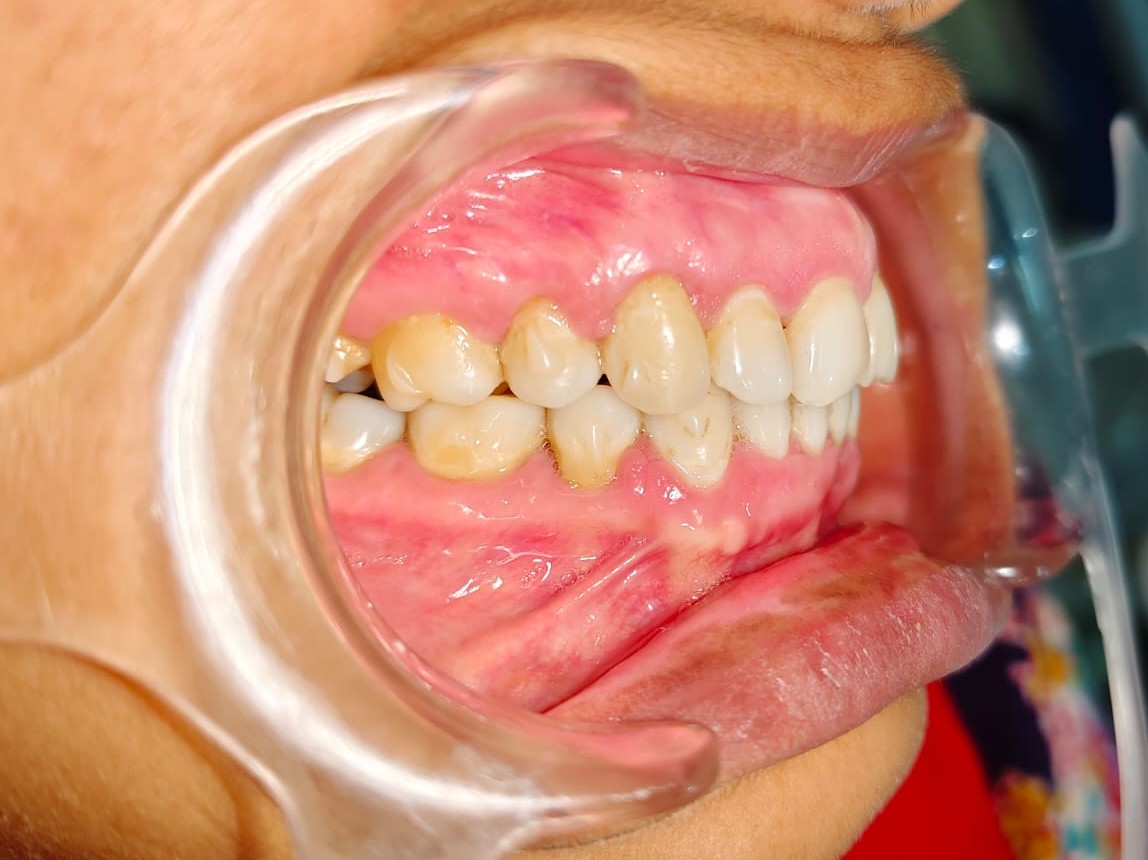

After/Before

See stunning smile transformation before and after

Before After